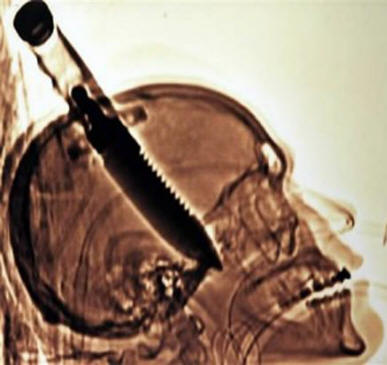

Vuonna 1998 Michael Hill vieraili ystävänsä kanssa Floridassa, kun yhtäkkiä kadulla hullu juoksi hänen luokseen ja … ilman syytä ilman syytä kiinni hänet paljaalla veitsellä. Michael itse tuli kotiin, eikö niin kahvalla, joka tarttui ulos päästäni, ja vain siellä järkyttynyt ystävä kutsui ambulanssin. Hill sanoi myöhemmin sen melkein ei tunne kipua päässä (vaikka tomografia osoitti sen veitsi tunkeutui aivoihin noin 20 cm!), ainoa asia huomautti, tämä on “lämpöä oikeassa silmässä”. Neljän tunnin leikkauksen jälkeen Michael siirrettiin jo osastolle ja muutamaa päivää myöhemmin purkautunut. Viime kädessä kaverin vasen käsi oli halvaantunut, mutta lääkärit sanovat, että hän pääsi silti helposti.